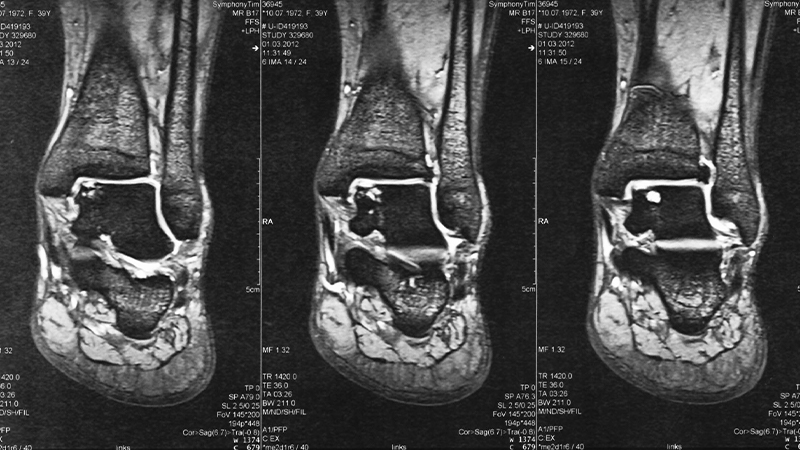

Ein Knorpelschaden am oberen Sprunggelenk ist meist auf ein akutes Trauma, eine Osteochondrosis dissecans (OD) oder eine chronische Instabilität des OSG zurückzuführen.

Operation Knochen-Knorpelschäden im Sprunggelenk.Arthrose der Talusgelenke. eine O- oder X-Beinfehlstellung, ein Meniskusschaden oder bestimmte Stoffwechselerkrankungen, können zu einem anfänglich noch begrenzten Knorpelschaden führen [5].Osteochondrosis dissecans wird medizinisch auch als osteochondral e Läsion bezeichnet. Um weitere Verletzungen auszuschliessen oder die Stellung der Beinachse zu ermitteln, werden allenfalls zusätzliche Abklärungen vorgenommen.Sie können dazu beitragen, vorhandene Knorpelschäden zu stabilisieren und die resultierende Symptomatik zu mildern, bzw. Lösen sich Knorpelstücke im Gelenk, kann dies zu einem Verschleiß führen (Arthrose).Das obere Sprunggelenk (kurz OSG) verbindet die Tibia (Schienbein) und die Fibula (Wadenbein) mit dem Talus (Sprungbein). Knorpelschäden am oberen Sprunggelenk (OSG) zeigen das Problem, dass auf relativ kleiner Fläche große Kräfte übertragen und ausbalanciert werden. Größere Defekte werden durch Knorpel-Knochen-Transplantationen (OATS-Plastik) behandelt. Eine Ausnahme stellt die Gelenkblockade durch abgelöste Knorpelfragmente ( Loose Bodys) dar. Reine Knorpelläsionen sind meist traumatisch und an der lateralen Talusschulter lokalisiert [1]. Ein Knorpelschaden kann mit Schwellung des Gelenks, Entzündung szeichen, Gelenkschmerzen und Knackgeräuschen ( Krepitation) verbunden sein. Häufige Ursachen für Knorpelschäden der Hüfte sind angeborene oder .Zu den Symptomen einer Knorpelschädigung in einem Gelenk gehören: Gelenkschmerzen – diese können auch im Ruhezustand anhalten und sich verschlimmern, . Die Beschaffenheit des Sprungbeinknochens verändert sich im Verlauf .Lassen Sie einen Knorpelschaden im Sprunggelenk von einem der führenden Spezialisten behandeln. Im Endstadium der Osteochondrosis dissecans löst sich ein Knochen-Knorpelfragment ( Dissekat) ab, was zur schmerzhaften Blockade des Sprunggelenks ( Impingement im Sprunggelenk) und langfristig zur Sprunggelenksarthrose führen kann. Im Jugendalter besteht auch die Vermutung, dass Knorpelschäden durch eine lokale Durchblutungsstörung des Knochens unter dem Knorpel entstehen können. Eine Operation kann notwendig werden, wenn neben den Bändern auch die knöchernen Anteile mitbetroffen sind. Die Therapie der Osteochondrosis dissecans (OCD) und der osteochondralen Läsion (OCL) sollte immer an das Ausmaß des Schadens und an das Alter des Patienten angepasst sein. Für die Auswahl des geeigneten Verfahrens ist die Kenntnis von Ätiologie und Art des Knorpelschadens von großer Bedeutung.

mit einem MRT (Kernspintomographie), erfolgt das abgestimmte medizinische Vorgehen.Häufigster Grund für Schäden am Gelenkknorpel im Bereich der Sprunggelenke ist ein Trauma.Die konservativen (nicht operativen) Therapiemaßnahmen für Knorpelschäden am Knie dienen der Funktionsverbesserung des Gelenkes.

Diagnose: Zur Diagnose wird das Kniegelenk geröntgt und (oder eine Kniegelenk-MRT durchgeführt.Behandlung Knorpelschaden am Knie Knorpelschäden und Knorpelknochenschäden im Bereich des Kniegelenks sind ein sehr häufig anzutreffendes Krankheitsbild. Der Arzt setzt lediglich 1,5 cm lange Schnitte seitlich des Sprunggelenks.Zu den biochemischen Ursachen für einen Knorpelschaden zählen unter anderem Stoffwechselerkrankungen.Unteres Sprunggelenk.